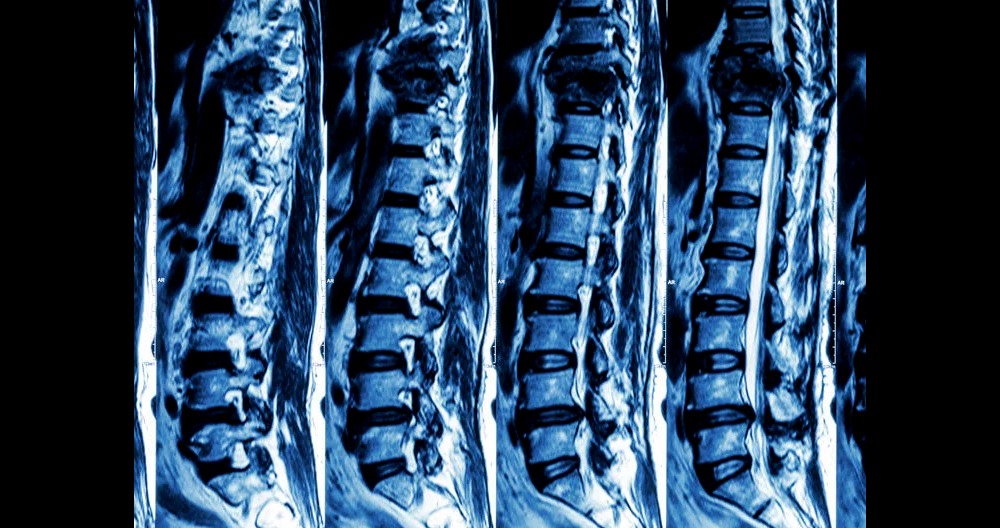

What is an MRI scanning for the Spine?

Magnetic resonance imaging (MRI), a test that uses a magnet field and pulses radio wave energy to take pictures of the organs and structures within the body, is called magnetic resonance imaging. In many cases, MRI provides information that is not available with the computed tomography scan (CT) scan. MRI may also reveal problems that are not visible with other imaging methods.

- Imaging organs and soft tissue internal structures (see the spine scan image to right)